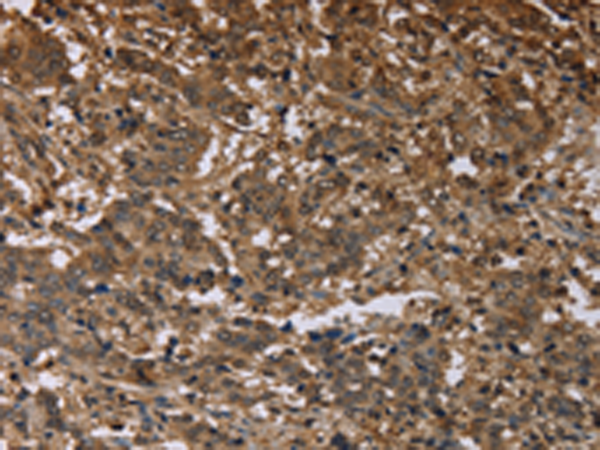

分类: 科研抗体货号: P05070别名: MTND1; ND1应用: WB,IHC反应种属: Human, Mouse, Rat